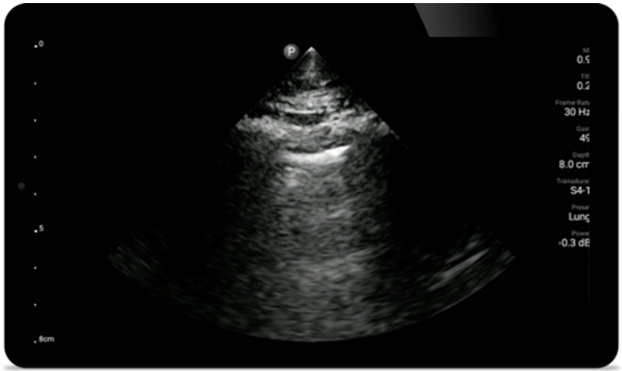

Lumify für die Beurteilung der Atemwege und Lungen

Die Lumify Point-of-Care-Ultraschalllösung kann die Erkennung des Endotrachealtubus in der Trachea erleichtern, Koniotomieverfahren unterstützen sowie bei der Diagnose von Pleuraerguss und interstitiellen Alveolarerkrankungen helfen.